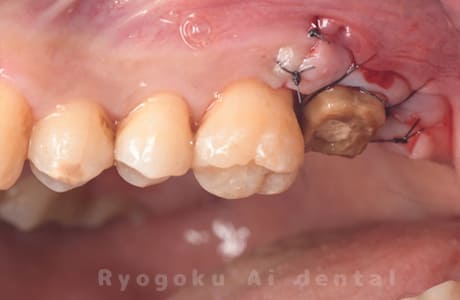

Case12

-

- 原因

- 縁下カリエス

- 治療内容

- クラウンレングスニング、ジルコニアクラウン修復

- 治療費用

- 約220,000円

被せ物の中から臭いがするとのことで、被せ物を外したところ大きな虫歯となっていました。このまま被せてしまうと被せ物が外れやすいため、埋まっている歯を出すためのクラウンレングスニング処置を行い、その後、ジルコニアクラウンで被せ物を行いました。